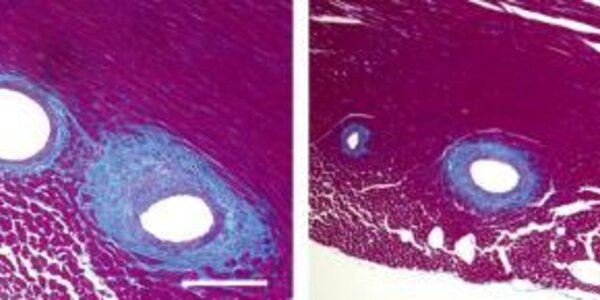

Utilizing Fat's Healing Properties In Heart Disease

Too much dietary fat is bad for the heart, everyone knows that by now, but not all fats are equal. The right kind of fat keeps the heart healthy, and a paper in The Journal of Experimental Medicine shows how it works. Unlike saturated fats discussed in popular media, unsaturated dietary fatty acids, such as eicosapentaenoic acid (EPA), are known to protect against cardiovascular diseases. However, the mechanism and the specific fat metabolites responsible for this protection were unknown.  A group of Japanese scientists have now discovered that mice engineered to produce their own EPA…